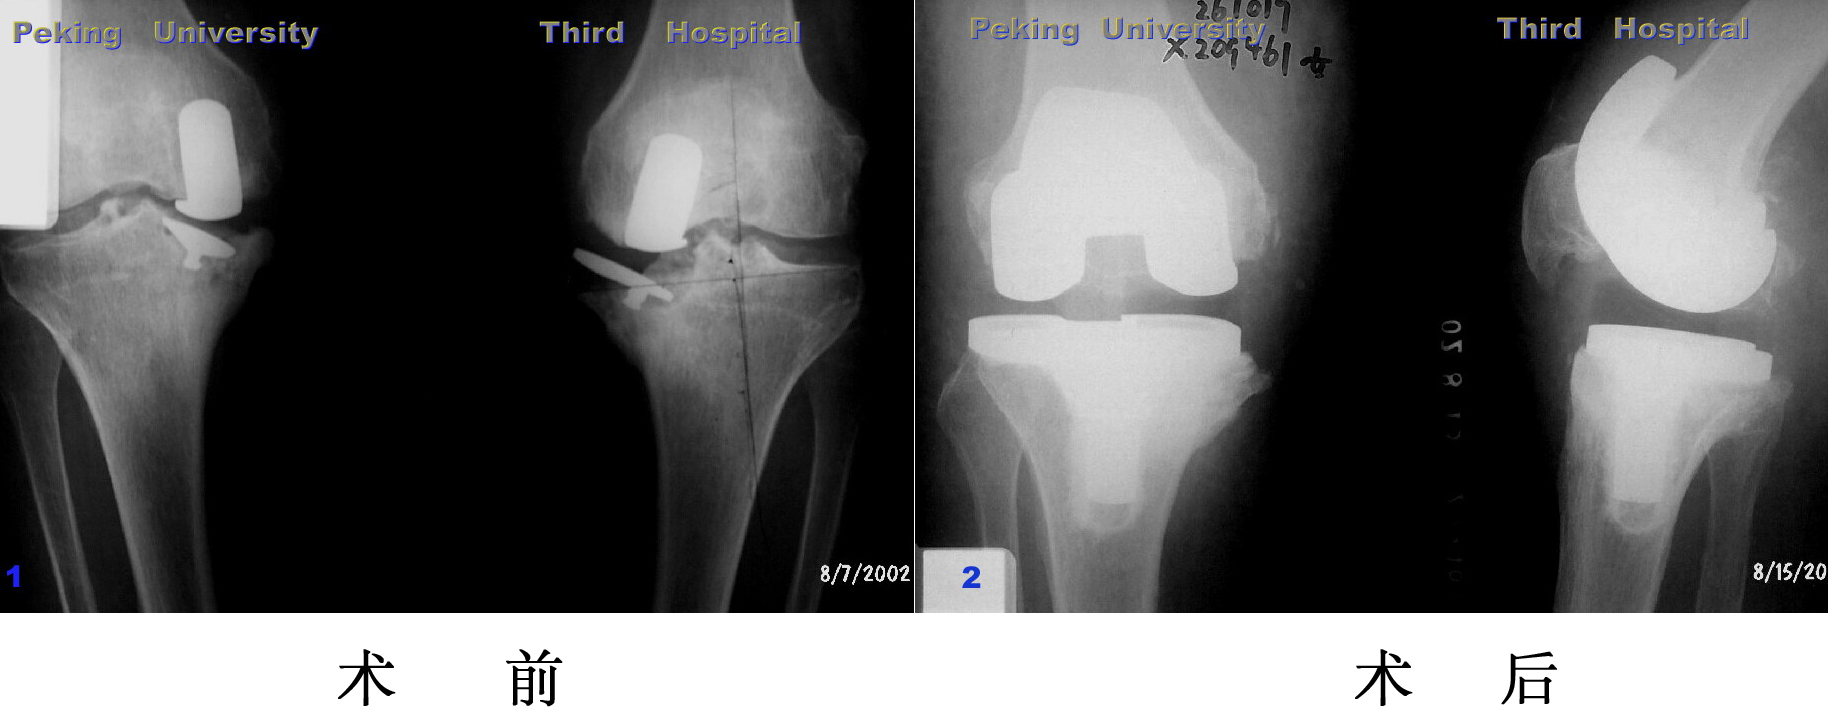

10年前因为膝关节骨性关节炎在我院接受关节置换手术,手术后疼

痛消失功能改善。2001年摔伤导致膝关节周围骨折,再次接受关节置换

手术,患者在病房过了90岁生日。现在关节功能良好,可以自己走路。